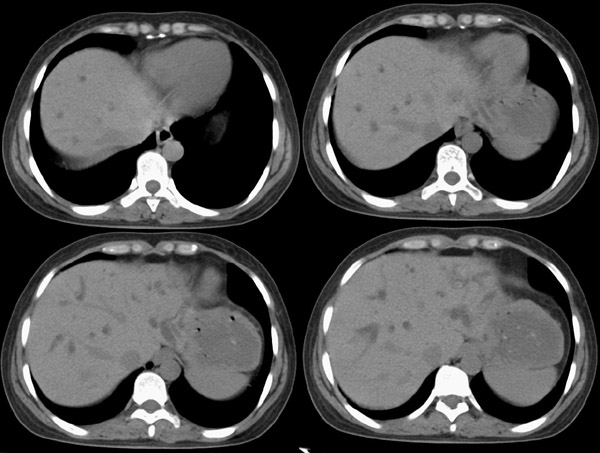

局部1mm薄层重建: